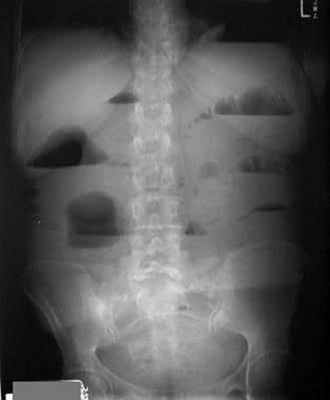

- Чаша Клойбера – горизонтальный уровень жидкости с куполообразным просветлением над ним, что имеет вид перевернутой вверх дном чаши. При странгуляционной непроходимости могут проявляться уже через 1 час, а при обтурационной непроходимости — через 3-5 часов с момента заболевания. Количество чаш бывает различным, иногда они могут наслаиваться одна на другую в виде ступенчатой лестницы.

- Кишечные аркады. Получаются, когда тонкая кишка оказывается раздутой газами, при этом в нижних коленах аркад видны горизонтальные уровни жидкости.

На рентгенограммах, полученных в положении стоя или лежа на боку, обычно видны горизонтальные уровни жидкости и газа (рис. 2). Рисунок 2. Обзорная рентгенограмма брюшной полости. Видны чаши Клойбера, уровни жидкости. Заполненные газом кишечные петли имеют вид опрокинутых чаш (чаши Клойбера). Они появляются при странгуляции через 1-2 ч после начала заболевания, при обтурации - через 3-5 ч. По размерам чаш Клойбера, их форме и локализации можно судить об уровне непроходимости.

При тонкокишечной непроходимости чаши Клойбера небольших размеров, ширина горизонтального уровня жидкости больше, чем высота столба газа над ним. Обычно наблюдается большое количество горизонтальных уровней с изменением их расположения в течение времени и перемещением жидкости из одной петли в другую. Горизонтальные уровни жидкости ровные. На фоне газа хорошо видны складки слизистой оболочки (складки Керкринга), принимающие форму растянутой спирали.

При непроходимости тощей кишки горизонтальные уровни жидкости локализуются в левом подреберье и эпигастральной области. При непроходимости в терминальном отделе подвздошной кишки уровни жидкости расположены в области мезогастрия.

При тонкокишечной непроходимости, кроме чаш Клойбера, на рентгенограммах видны растянутые газом кишечные петли, принимающие форму «аркад» или «органных труб», похожих на перевернутые буквы J и U.

При толстокишечной непроходимости горизонтальные уровни жидкости расположены по периферии брюшной полости, в боковых отделах живота, и их меньше, чем при тонкокишечной непроходимости. Высота чаш Клойбера преобладает над шириной. На фоне газа видны полулунные складки слизистой оболочки («гаустры»). Уровни жидкости не имеют ровной поверхности («зеркала»), что обусловлено наличием в толстой кишке плотных кусочков кала, плавающих на поверхности жидкого кишечного содержимого.

При динамической паралитической непроходимости, в отличие от механической, горизонтальные уровни жидкости наблюдаются одновременно как в тонкой, так и в ободочной кишке. Перемещения кишечных уровней со временем из одного колена кишки в другое не наблюдается. При динамической спастической непроходимости по ходу тонкой кишки видны мелкие чаши Клойбера, расположенные цепочкой слева сверху вниз и вправо.